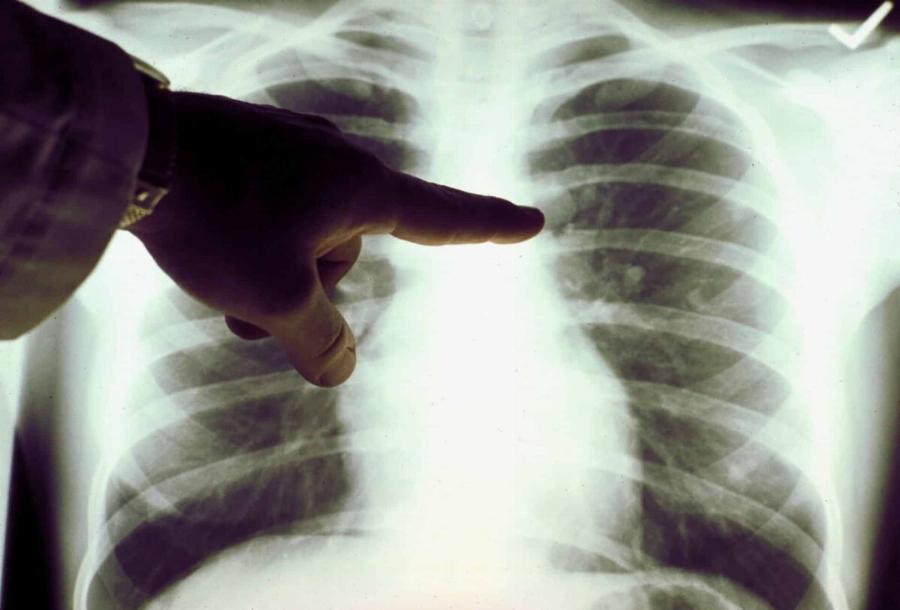

Καρκίνος του πνεύμονα: Πρόκειται για ένα συνηθισμένος και θανατηφόρο καρκίνο.

Όπως και πολλοί άλλοι καρκίνοι, ο καρκίνος του πνεύμονα μπορεί να ανιχνευθεί στο αρχικό στάδιο (στάδιο 1), οπότε είναι σημαντικό να αναγνωρίσουμε όλα τα συμπτώματα.